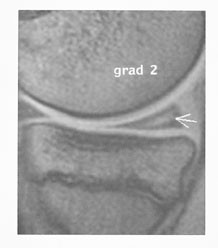

Det er tre typer menisklesjoner som kan påvises ved MR (5). Figur 2 viser skjematisk ulike typer av meniskdegenerasjoner. Disse viser seg som høysignalområder i menisken. Type 1 gir et lite intrameniskalt høysignal. Type 2 gir et lineært intrameniskalt høysignal som kan tangere meniskens overflate (fig 3). Ved type 3 sees et høysignal som bryter meniskens overflate. Det er denne typen vi beskriver som meniskruptur og som artroskopøren vil se som ruptur. Type 1 og type 2 oppfattes som degenerative forandringer uten patologisk betydning. Disse blir derfor ikke beskrevet. De er svært vanlige og starter allerede i barneårene.